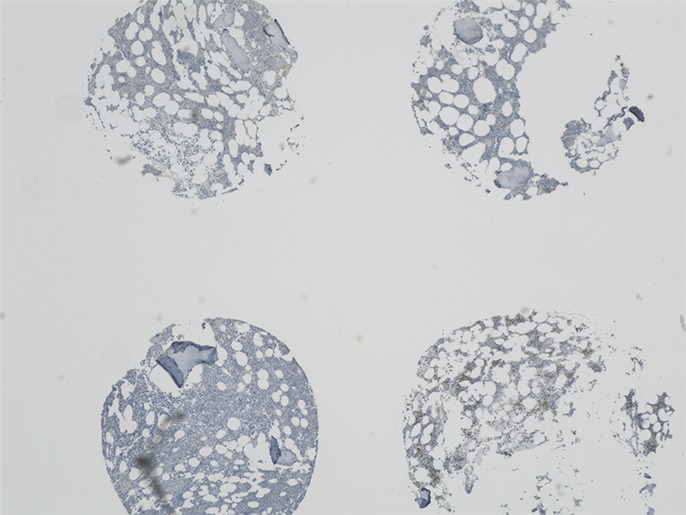

この研究グループ独自の成果として、特別に開発したMDSの骨髄パンチ生検のTMA(組織マイクロアレイ)がある。このTMAには、AML(急性骨髄性白血病)患者の生検と正常対照者の生検が含まれており、直接比較することができる。TMAに関する免疫組織化学的研究を評価するうえで、蛍光顕微鏡BZシリーズの大きなメリットとしては、TMA上のひとつのサンプル、あるいは複数のサンプルをまとめて1枚の画像に収めることができる点が挙げられる。

ガッターマン博士は、「2 mmのコアを1枚の画像で表示するためには、画像連結機能が特に重要です」と説明する。